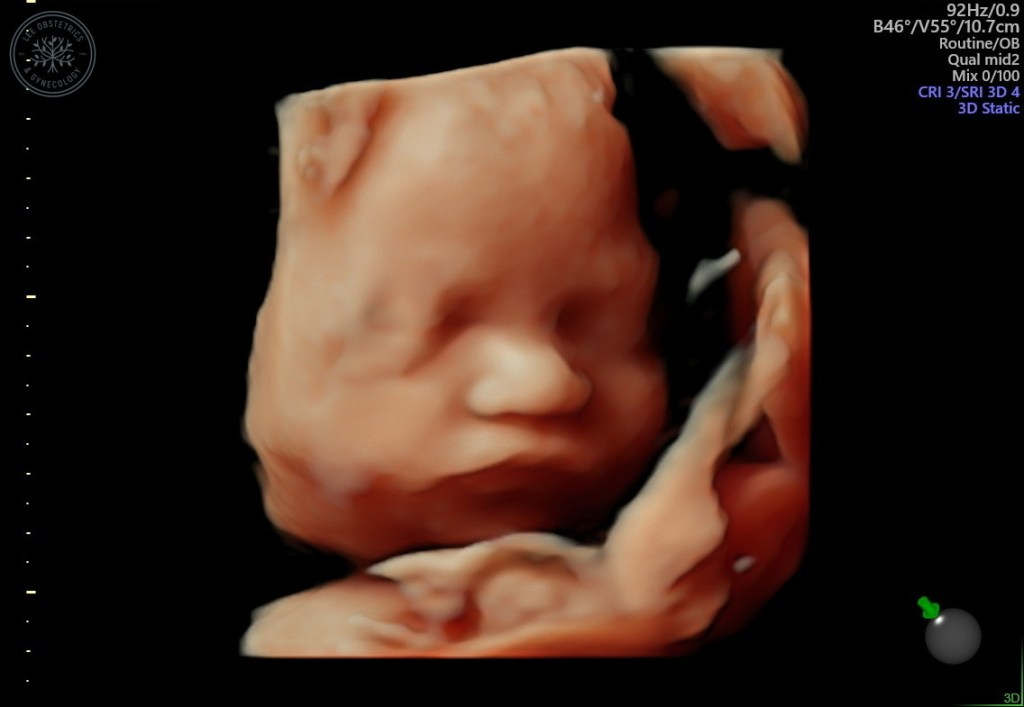

As I gaze at Addie’s ultrasound pictures, I find myself daydreaming about holding her, feeding her, and watching Chet and Daniel love on her. My heart is so full already. Now we need to spend the next 10ish weeks preparing the nursery, preparing Chet, and remembering Ginny as we embrace all we can of this pregnancy in hopes of bringing little sister home.

Addie’s Anatomy Ultrasound

I know too much. Even though the 20 week anatomy ultrasound went really well in Ginny’s pregnancy, I was scared for what we might learn this time around. There is so much that can go wrong. In fact, when things go right, it feels like a miracle. I know so many people whose anatomy scans were their “before and after” moment. That’s the moment that divides the “before” – when things were all good and the “after” – when they are faced with hardship. I hoped and prayed that this scan would not be our 2nd “before and after” moment (our 1st was when we found out Ginny had died).

I didn’t want to be scared or to have those thoughts. I wanted what we had with Ginny’s anatomy scan; I wanted to just enjoy seeing my little girl wiggle and see her sweet features for the first time. But I have to face the reality that that isn’t my story anymore. All the positive thinking in the world can’t make me unlearn what I now know, and it can’t magically erase trauma. I’ve lost my naivety. And that’s okay. It’s hard, but it’s okay.

I rescheduled the ultrasound from Wednesday afternoon to Monday morning. I wouldn’t be able to wait and wanted to get it over with as early in the week as possible. I was eager to see Addie again. I hadn’t had an ultrasound since week 9. I was excited to get pictures and watch Daniel see her move on screen. But mostly I wanted relief in knowing she was developing and growing. Daniel’s parents had been in the room with both Ginny and Chet’s anatomy scans. We wanted to make it 3 out of 3, so they planned their visit here to coincide with the appointment. Daniel’s dad stayed home with Chet while his mom came along to the ultrasound. Unfortunately when we arrived, we were informed she may not be able to come in. The sonographer wanted minimal distractions. This was a high risk ultrasound with very precise measurements and sometimes tricky angles. There were many pictures and measurements required in a limited time. We were reminded that this was not a scan for fun pictures. What was already anticipated to be a really tense appointment felt even more so.

Ultrasounds can be triggering since it was in an ultrasound that we were given the news that Ginny died. I knew I needed to let the sonographer know from the very beginning that we had a stillbirth so she may have more understanding if things get hard. It is extremely challenging to meet someone new, already be so anxious, be in the same cold, triggering environment you were in when you got the worst news, and speak out loud, “I should tell you that we had a stillborn daughter at 35 weeks.” All that while trying not to break down in tears and being in a very physically vulnerable position on an ultrasound bed with pants off and stomach bare. She told me she already knew of my stillbirth from my chart and then said some sympathetic words.

She proceeded to start taking measurements. Little by little we saw more and more of Addie’s body – her spine, her abdomen, her legs and arms, her head. We saw her little movements. It was a blessing to see her. But with each angle we saw, I was trying to analyze if everything looked healthy. I was trying to read the screen as well as the body language of the sonographer. I’m unqualified, but she knows what she’s seeing. She just can’t say – good or bad. She kept going back to the heart. In Chet’s anatomy scan I remember so clearly seeing 4 chambers of his heart. I remember feeling relieved because it looked so normal. Now with Addie, I was only seeing 3 chambers. The sonographer said she needed Addie to move positions so she could get a better angle. We tried poking her, turning to my side, even getting up and moving around. Addie wouldn’t cooperate. The sonographer gave us the okay to invite Daniel’s mom back as we tried a few more times. No luck. We would likely have to come back for another ultrasound. My mind was going through all the scenarios. Maybe if we are lucky and she lives, she will need heart surgery right away. Maybe she will eventually need a heart transplant. I just want her to live.

As we waited to meet with the Maternal Fetal Medicine (MFM) doctor who would give us the results, Daniel and I spoke about how we really wished this was more fun. We forgot how nerve wracking the whole process was. We lamented how our minds go to the worst outcomes. I’m glad his mom was there for support.

The MFM came in and said everything she saw looked really good, but she didn’t have a good picture of the heart. She asked us to follow her into another ultrasound room so she could take a look herself. I laid back down, and she was able to see what she needed to. Everything looked great! Her heart looked good! I was relieved. I’m so grateful for our MFM; she has listened to my concerns and she took the time to do the ultrasound herself. I’m so glad I didn’t have to come back on another day and wait anxiously not knowing if Addie was healthy.

As relieved as I was that we got a good report, I am not as relieved as I feel I should be. As I mentioned before, Ginny’s anatomy scan also looked great. We are all too aware that things can go wrong in the 2nd half of pregnancy. I am still trusting God with our little girl no matter what. She is His, and His will be done. I really really hope to get to bring her home in September. Everything so far is looking good for that to happen, but I know I won’t feel safe until she’s in my arms. I can’t wait for that day!